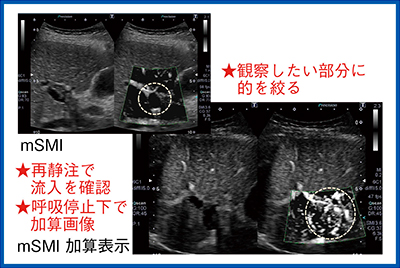

そこで,造影剤を使ってさらに詳細に評価した。ソナゾイドによる造影超音波検査のポイントは,高いフレームレートで観察を行うためにROIを絞って観察をすることである。治療部位が高エコーで見えにくい場合には,造影剤の再灌流の様子を加算するMicro Flow Imaging(MFI)で造影剤が流入する場所を確認し,その部分をlow MIモードで詳細に観察する。また,輝度が低くわかりにくい場合には,2画面表示にしてBモードで関心領域を確認し,そこに注目してMFIで任意断面の濃染・血管構築を観察する。このように,目的を持って検査方法を使い分けることが大切である。

造影SMIと非造影SMIを比較する。造影することで感度が良くなり血管情報は多くなるが,ブルーミングにより血管の不整像が出現する(図4b)。一方,非造影SMI(図4a)を見ると,観察したい領域の淡い血流も描出されており,造影検査に匹敵する感度があることがわかる。細かい血流を観察するためには全体像を見るのではなく,的を絞ってROIを設定することが重要である。